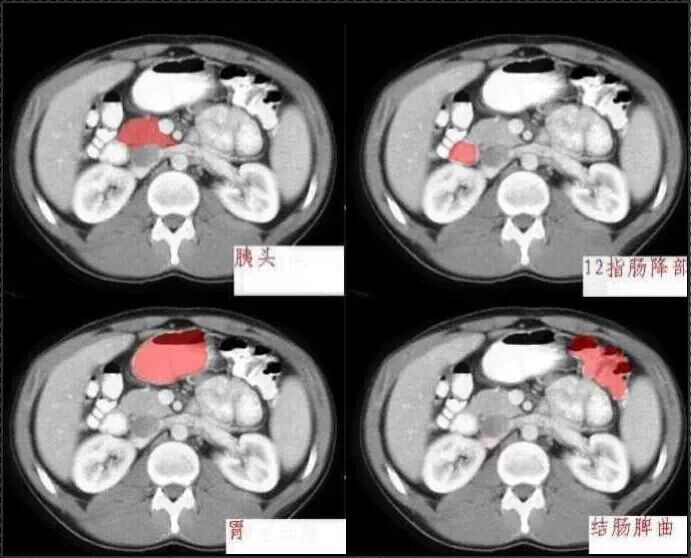

十分钟学会腹部CT解剖(多图)